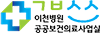

경기도의료원 이천병원, 스텐트 시술로 협심증 환자 치료 성공 작성자:이금호 2019.09.09 VIEW.624 No.56 |